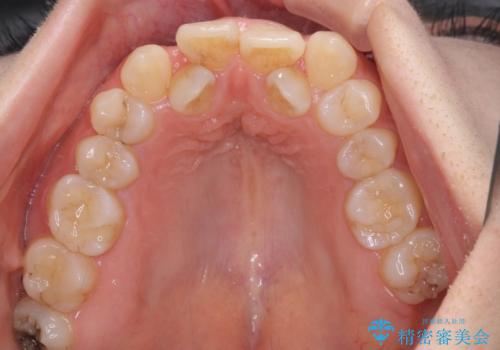

- 前歯の著しいデコボコを気にして来院された患者様です。

上顎の左右側切歯(前から2番目)が裏側に隠れいてる状態で、咬み合わせや清掃性に大きな問題が認められました。

叢生が著しいため、左下以外の第一小臼歯3本を抜去し、目立たないワイヤー装置にて矯正治療を行うこととしました。

これほど顕著に裏側に隠れいてる歯ですと、仕上がったときに両隣の歯と軸に差が認められることが多いのですが、殆ど違和感のない歯並びを達成することができました。